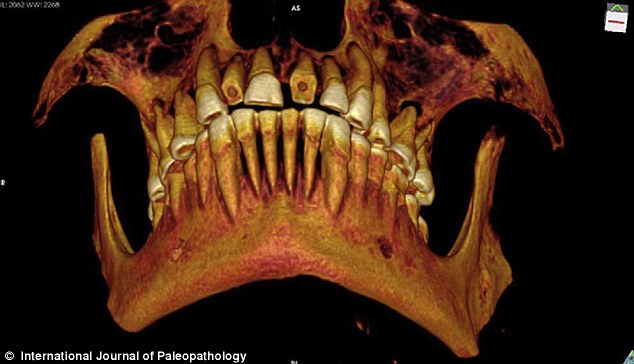

研究人員通過CT掃描圖片觀察木乃伊的口腔,并重建了一張顯示磨損門牙的3D圖。

《古病理學(xué)國際期刊》的文章稱,來自加拿大西安大略大學(xué)的安德魯·韋德利用一種新型高分辨率CT儀掃描木乃伊的牙齒和身體,并且根據(jù)掃描片重建了3D圖以進(jìn)行更為細(xì)致的研究。從CT掃描片可以看到,木乃伊的一顆牙齒齲洞里塞著一塊亞麻布團(tuán)。這塊亞麻布之前可能經(jīng)過無花果汁液或雪松油等藥物的浸泡,隨后被塞入下顎第一、二顆臼齒中間,也就是最大、也是最疼的齲洞里。這么做既能起到抵擋食物殘渣進(jìn)入齲洞的屏障作用,又能利用亞麻布上的藥物緩解疼痛。